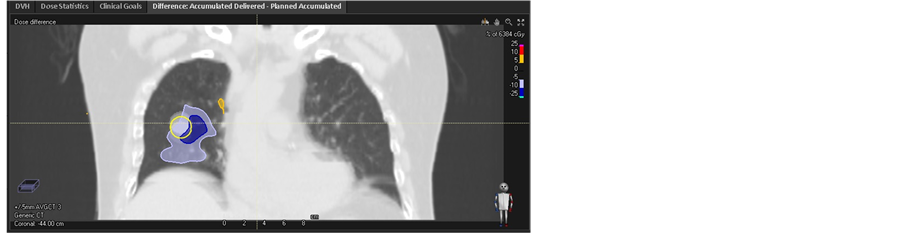

The accumulative dose was calculated by sum up total phase dose distribution using the corresponding DVF. The dose difference and DVH between accumulative dose and planned dose on target were shown in Figure 5. In fact, the D98 of cumulative dose for GTV based CTavg_only and MIP CT are 53.48 Gy and 57.68 Gy, the corresponding discrepancy compared to planned dose reach to −11% and −4% respectively. While the D98 of cumulative dose for GTV based CTavg_muscle and CTavg_tumor are acquired as 60.19 Gy with discrepancy 0% and 59.73 Gy with discrepancy −1%, which is close to the initial plan dose. The dose discrepancy on GTV between cumulative dose and initial dose are larger for MIP CT and CTavg_only sensitivity of proton range and motion of the tumor uncertainties. While the corresponding discrepancy are relatively small for CTavg_muscle and CTavg_tumor, which is the reason that the proton plan was often implemented on CTavg_muscle or CTavg_tumor in most of the proton clinic.

However, in presence of proton range uncertainty of +/−3.5% [20] [21] , the dispersion of DVHs significantly increase based both CTavg_tumor and CTavg_muscle. DVH for GTV on each phase was displayed on Figure 6. In the worst case, GTV D98 decrease to 51.96 Gy in phase −5 mm on CTavg_tumor based plan, while D98 of GTV decrease to 55.96 Gy in phase −5 mm on CTavg_muscle based plan. Detail result was listed in Table 2. Figure 7 shows the GTV coverage difference between the accumulative dose and planned dose.

Figure 5. Dose difference between accumulation and initial plan based on (a1) CTavg_tumor, (b1) CTavg_muscle, (c1) CTavg_only, (d1) MIP, GTV comparison DVH between accumulation and initial plan based on (a2) CTavg_tumor, (b2) CTavg_muscle, (c2) CTavg_only, (d2) MIP CT.